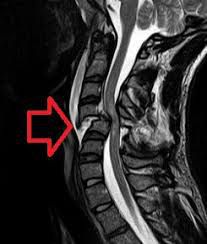

What causes neurogenic shock? Causes of neurogenic shock include: Spinal cord injury (the most common cause). Autonomic nervous system toxins. Guillain-Barré syndrome. Spinal anesthesia. Transverse myelitis